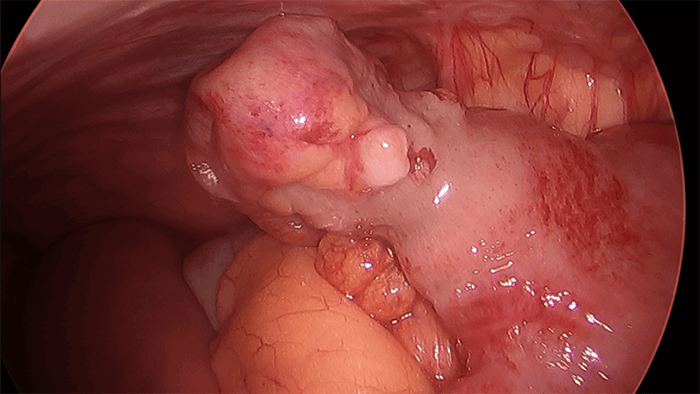

Figure 4. Another view of the Meckel diverticulum

In adults, these ectopic tissues, if present, are likely atrophied, and the so-called symptom of painless bleeding is typically absent.7 In this case, there was an adhesive band from this patient’s Meckel diverticulum to the JJ anastomosis of the Roux-en-Y bypass, causing a distal pSBO and leading to dilation of the biliopancreatic limb and the Roux limb. The thick adhesive band was lysed, the mesentery of the diverticulum was taken down with the Harmonic scalpel, and the diverticulum itself was transected with an endoscopic stapler.